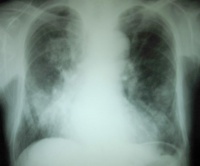

血常规尿常规粪常规等,心电图胸片超声心动图非常有意义,可以判断心功能损伤的程度。尤其是是超声心动图,可测量左室射血分数(LVEF),正常LVEF值>50%,LVEF≤40%为收缩期心力衰竭的诊断标准。一些实验室指标,比如心肌酶脑钠肽等对于心功能不全/心衰的判断也有意义。此外尚有放射性核素检查等多项检查。根据临床需要可以酌情考虑选取。心功能不全的辅助检查与心力衰竭是相同的,可以参考。